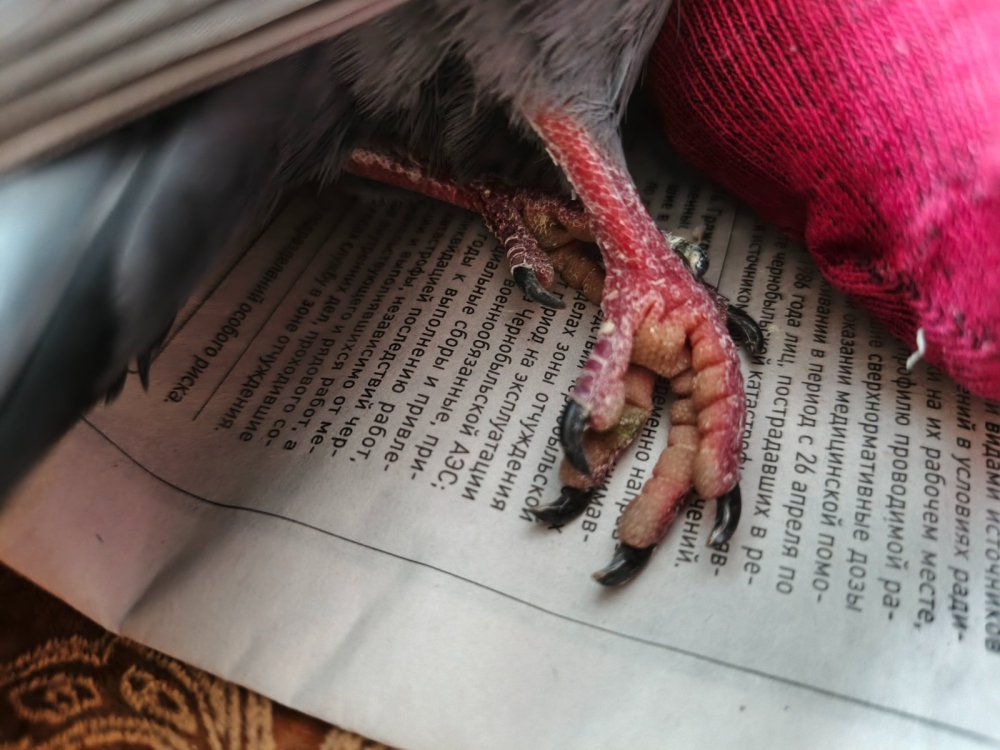

Добрый день! Прошу консультации! В мороз -37 (недели 1,5 назад) подобрала слётка: летать еще летал, а ходил с большим трудом. Дома отгрела, накормила. Припадает на лапки, предпочитает лежать, чем стоять на лапках, если приходится ходить то на "цыпочках" или на коготочках, на серединку лапки не наступает. Визуально ни припухлостей, ни ран нет (сравнивала со вторым слётком, которого подобрала вместе с ним и который нормально ходит). В остальном: летает, кушает хорошо, бодренький, активный голубенок. Может есть какие-то рекомендации, идти с ним некуда...